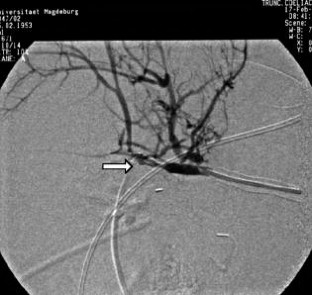

Wir berichten über das diagnostische und therapeutische Vorgehen anhand von 7 Patienten mit Blutungen aus der A. gastroduodenalis (n=5) nach pankreaschirurgischen Interventionen bei Pankreaskopfkarzinom, Rezidiv eines Liposarkoms und chronischer Pankreatitis, der A. hepatica communis (n=1) bei chronischer Pankreatitis und der A. mesenterica superior (n=1) nach akuter Pankreatitis. Anhand von 4 Kasuistiken werden unsere Erfahrungen mit der Implantation von Stentgrafts (Hemobahn®-Prothesen) vermittelt. Den Vorteil der Stentgrafts sehen wir in der sofortigen Blutstillung bei fehlendem Kontakt der Endoprothese zu infiziertem Gewebe und Erhalt der Perfusion des abhängigen Organs. Unsere positiven Erfahrungen mit diesen interventionellen Therapieverfahren erfordern jedoch weitere klinische Untersuchungen, wobei im Mittelpunkt die Indikationen, die technische Erfolgsrate, die stentbedingten Komplikationen und die Langzeitverläufe stehen sollten.

Spontaneous or postoperative hemorrhage into the abdominal cavity due to inflammatory vessel arrosion represents an uncommon but menacing situation. According to the literature, such hemorrhage is associated with a lethality of nearly 2%. Therapeutical options include reoperation and interventional radiological techniques such as endovascular catheter techniques with stent graft implantation or the embolization of vessels. We report on the management of seven cases with hemorrhage either from the gastroduodenal artery (n=5) following pancreatic surgery for pancreatic carcinoma, liposarcoma, and chronic pancreatitis or from the common hepatic artery (n=1) and the superior mesenteric artery (n=1) following chronic pancreatitis. The present article describes our experiences with stent graft implantation (hemobahn prosthesis) in four cases. Based on these experiences, we see the advantages of stent grafts in primary hemostasis without any contact to infected tissue and the preservation of regular perfusion. However, further clinical data are required focussing on indication, technical success rates, stent-related complications, and long-term outcome.

Abb. 3